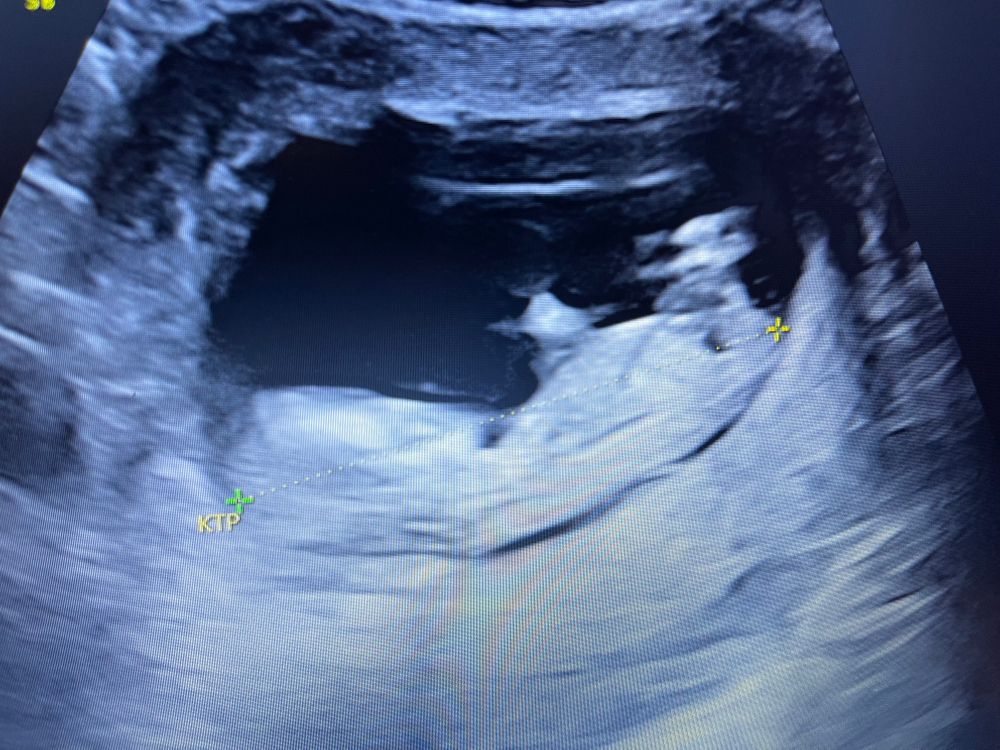

Вот фото с узи, может кто понимает, как они определяют)))) Точно скорее всего мальчик?

Лично увидеть нужно фото хозяйства. Если оно есть, то сомнений не будет. Плюс оборудование плюс врач. Мне не соврали ни в первый раз ни во второй. Но у меня мальчки прям мальчки не прячутся и фиг там спрячешь ))

Мой мальчик в 12 и 3.

Мальчик 99 и 9 судя по УЗИ вашему . Очень задран половой бугорок . У девочек так не бывает . Мне оба раза в 10 недель правильно про сказали . В этот раз ещё и нипт подтвердил потом